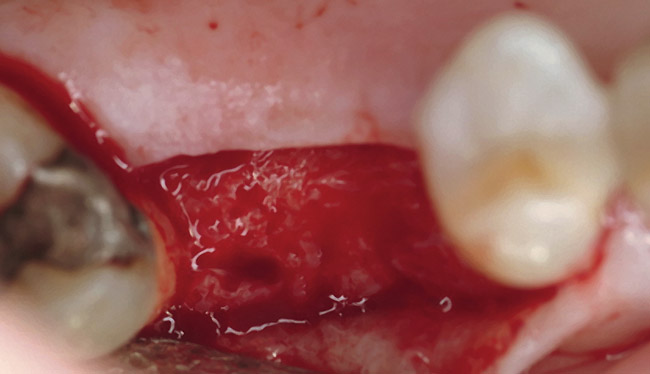

The patient was a 66-year-old man who required removal of the three mandibular right molars due to rampant caries and attachment loss. Following flap reflection and extractions, the sockets were debrided with both ultrasonic and manual instrumentation (Figure 10). The sockets of the first and second molars were augmented with rhBMP-2/ACS. The site of the third molar was obturated with a noncrosslinked, collagen plug for hemostatic purposes only.